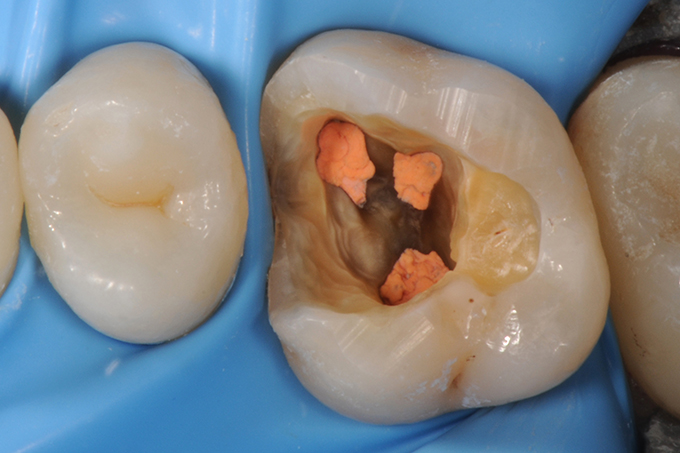

Tooth with new RCT in place.

Build-up with remodeled margin (according to Dietschi, D., Spreafico, R., 1997) and final preparation of the tooth.